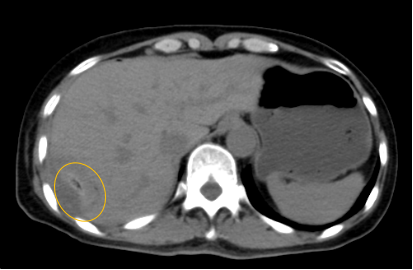

入院后,影像診療中心立即給李女士完善了CT和MR檢查,發(fā)現(xiàn)病變位于肝包膜下,臨近膈肌,消融治療過程中有并發(fā)損傷膈肌的可能,難度較大,但是采用精準影像定位是可以完成的。陳寶瑩主任立即與腫瘤三病區(qū)劉金鵬主任聯(lián)系,并與影像微創(chuàng)治療小組進行MDT討論:患者為卵巢癌肝右葉包膜下單發(fā)轉移瘤,最長徑不超過3cm,患者對局部治療的主觀愿望強烈,符合消融治療專家共識,遂制定了影像引導下局部消融治療聯(lián)合全身治療的綜合治療方案。

針對這個特殊部位的腫瘤,要想消融完全,那么膈肌損傷的風險就很高,陳寶瑩主任帶領影像微創(chuàng)亞專業(yè)組成員仔細閱讀CT圖像,設計進針路徑,結合MR圖像確定腫瘤活性范圍,制定了周密而詳盡的消融計劃。臘月二十九,即住院第二天影像微創(chuàng)治療小組圓滿為患者完成了腫瘤微波消融治療,觀察24小時后出院回家過年。術后48小時隨訪患者無明顯不適,術后7天隨訪,患者肝功、血常規(guī)等各項指標均恢復正常。